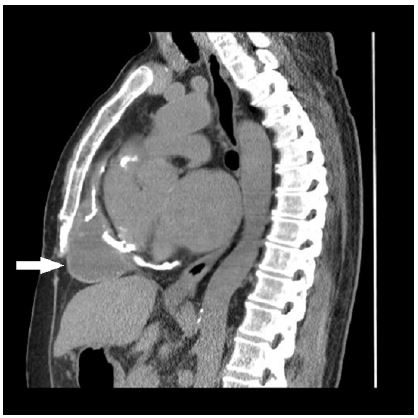

Among the results of the investigations carried out, the following are worth mentioning: Echinococcus IgG serology (by chemiluminescence immunoassay method) resulted negative; nucleic acid amplification for Entamoeba histolytica/dispar on feces resulted negative; QuantiFERON-TB Gold Plus (QFT®-Plus; Qiagen) resulted positive, suggesting a tubercular infection (at least a latent infection). A contrast-enhanced chest CT scan ruled out pulmonary parenchymal involvement but revealed extension of the mediastinal collection both above and below the diaphragm, with contact noted with both the pericardium and the hepatic capsule. Notably, the cyst capsule did not show ring enhancement after contrast, as was expected by a collection of infectious origin (Figure 1). Moreover, the chest CT showed numerous calcifications in the pericardial area (Figure 2). Following multidisciplinary discussion, on November 16, 2022, the patient underwent surgery for the removal of the cystic formation. Intraoperative samples revealed acid-fast bacilli, identified by nucleic acid amplification (Xpert® MTB/RIF; Cepheid) as rifampin-susceptible M. tuberculosis complex, subsequently confirmed by traditional mycobacterial culture to be pan-susceptible M. tuberculosis. Sputum and bronchial aspiration cultures were negative for acid-fast bacilli. Based on the findings from the intraoperative samples, antitubercular therapy was started using a standard intensive phase regimen (rifampin 10 mg/kg/day, isoniazid 5 mg/kg/day, pyrazinamide 25 mg/kg/day, ethambutol 20 mg/kg/day).

Figure 1: Axial chest CT scans before (A) and after (B) contrast enhancement. The cyst capsule (marked with a white arrow) do not show ring enhancement after contrast.